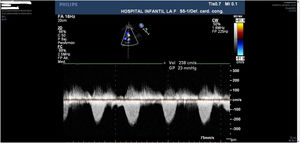

El último control clínico-ecocardiográfico ambulatorio disponible muestra una paciente asintomática con estenosis pulmonar valvular leve (gradiente 23 mmHg) con anillo pulmonar de 21 mm (z = + 0,02) e insuficiencia valvular leve (figs. 5 y 6).